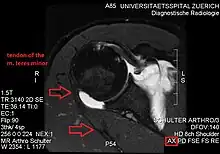

Atrophy of the teres minor muscle is often a consequence of a rotator cuff tear, but common isolated teres minor atrophies have also been found. A quadrangular space syndrome causes excessive and or chronically compression of the structures which pass through this anatomical tunnel. The axillary nerve and the posterior humeral circumflex artery pass through the space. People affected note shoulder pain and paresthesia down the arm first and foremost in abduction, extension, external rotation and overhead activity. Selective atrophy of the teres minor muscle has been seen and pulled together directly with compression of the corresponding axillary nerve branch or posterior humeral circumflex artery. Fibrous bands, cysts of the glenoid labrum, lipoma or dilated veins can occupy the quadrilateral space pathologically. Similar symptoms are common with anterior shoulder dislocation, humeral neck fracture, brachial plexus injury and thoracic outlet and inlet syndrome. It is important to include those pathologies for a complete as possible differential diagnosis.

Ultrasonography is a tool to detect a fatty degenerative atrophy of the teres minor and shows in affected muscles increased echogenicity and betimes a slight reduction in muscle bulk. MR imaging helps to consolidate the diagnosis of neurogenic muscle atrophy. Extracellular edema after traumatic events causing neural damage show an increased signal intensity on T2-weighted MRI sequences and normal intensity on T1-weighted sequences. Posterior humeral circumflex artery compression and reduced blood flow in stressful arm positions and or maneuvers can be diagnosed by a Doppler ultrasonography. The nerve should be detected adjacent to the vessel. In an elevated arm position the axillary neurovascular bundle can be seen at the posterior axillary fold just before it perforates the deltoideus, while the posterior course is well visible in the neutral position. For a detailed assessment of the artery, a MR angiography is required. The major task of an ultrasonographic examination is to rule out any space occupying mass. Additional electromyography is helpful to reveal any decelerated nerve conduction velocity, and thus denervation of the concerned muscle.[6]